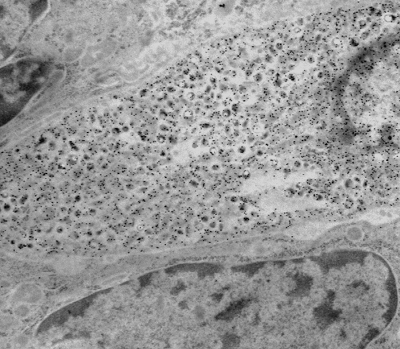

Protein A gold labeling of a prostatic endocrine-paracrine cell demonstrating localization of calcitonin (inset) to the neuroscretory granules.

Paraffin embedded tissue (same tissue) sections are cut and screened by light microscopy using a streptavidin-biotin technique to determine the appropriate antibody concentration to be used for the EM immunogold procedure. Ultrathin sections from the same block(s) are cut, incubated with primary antibody and then later incubated with Protein A gold particles (size range is 5 nm to 20 nm). The gold particles bind to the Fc portion of the antibody and are detected by EM. A variation of the large block "pop-off" technique for immunoelectron microscopy is also available.